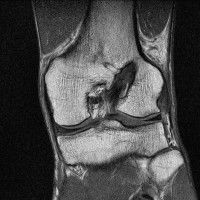

무릎 mri 간단히 봐주실 수 있으시나요 ㅠㅠ

안녕하세요 8년전 십자인대 수술하고 최근 무리한 운동에 무릎 불편감이 생겨서

mri 찍었습니다.

진단결과는 첫 찍은 병원에서 활액막염 이라는 진단을 받았습니다. 혹시 봐주실 수 있으실까요?

올라온 MRI가 단편적이라서 정확한 진단에 어려움이 있지만 십자인대에는 큰 이상이 있지는 않은것 같으며, 무릎관절내 물이 있는 것으로 보아 활액막염의 진단이 맞을 것 같습니다.

하지만 단편적인 영상이기 때문에 촬영병원에서 정확한 판독지 등을 받으시는 것이 좋겠습니다.